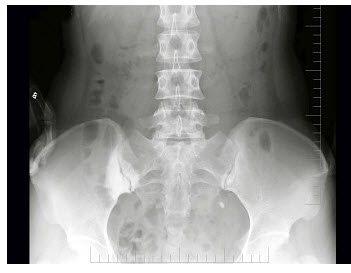

12、单项选择题

女,26岁,骶髂部疼痛2年余,间歇发作,结合图像,最可能诊断是()

A.致密性髂骨炎

B.化脓性髂骨炎

C.结核性髂骨炎

D.强直性脊柱炎

E.骶髂关节退行性变